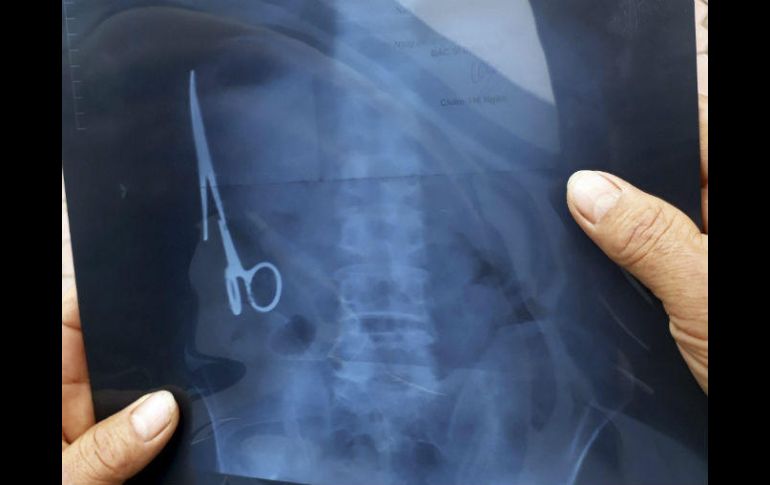

Retiran unas tijeras que llevaban 18 años en el estómago de un vietnamita

Radiografía tomadas tras accidente de tráfico revelaron la presencia del instrumento

Las tijeras se encontraban oxidadas, en la parte izquierda del estómago. EFE /

BANGKOK, TAILANDIA (03/ENE/2016).- Un vietnamita ha vivido 18 años con unas tijeras que los médicos se olvidaron en su estómago y de cuya presencia nadie se había dado cuenta hasta el mes pasado, cuando sufrió un accidente de tráfico y le hicieron una radiografía.

La intervención quirúrgica para retirar el instrumento médico de 15 centímetros de largo se realizó el sábado pasado en un hospital de la provincia de Thai Nguyen, en el norte de Vietnam, y duró unas tres horas.

Las tijeras se encontraban oxidadas, en la parte izquierda del estómago, según los doctores que el intervinieron citados por el medio vietnamita Tuoi Tre.

El paciente, un hombre de 54 años, nunca había sentido molestias por la presencia de las tijeras que se olvidaron en su estómago en junio de 1988, cuando le intervinieron en el Hospital General Bac Kan por otro accidente de tráfico.